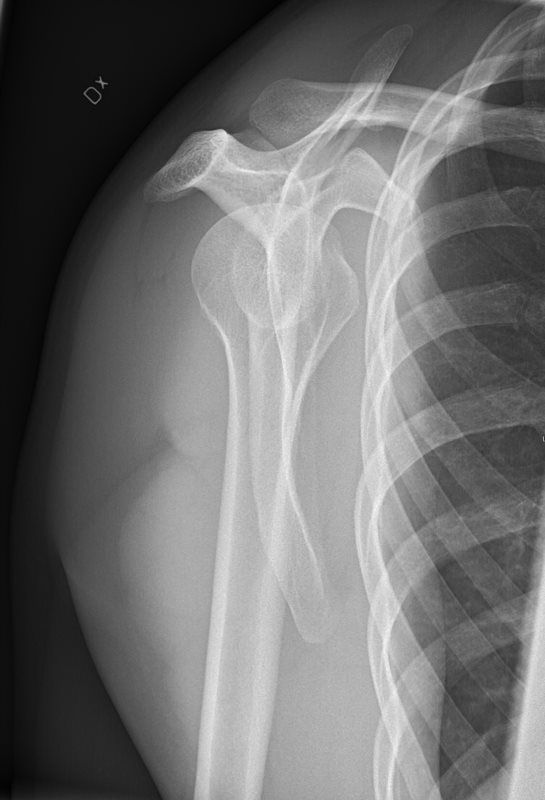

Our primary focus is Interventional Pain Management.